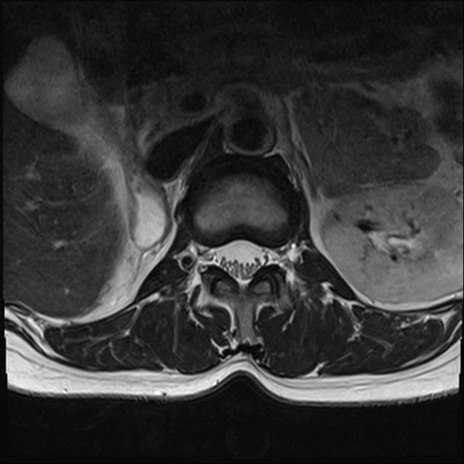

【整形】TIPS症例4 腰椎MRI T2WI(横断像)

横断像と矢状断像